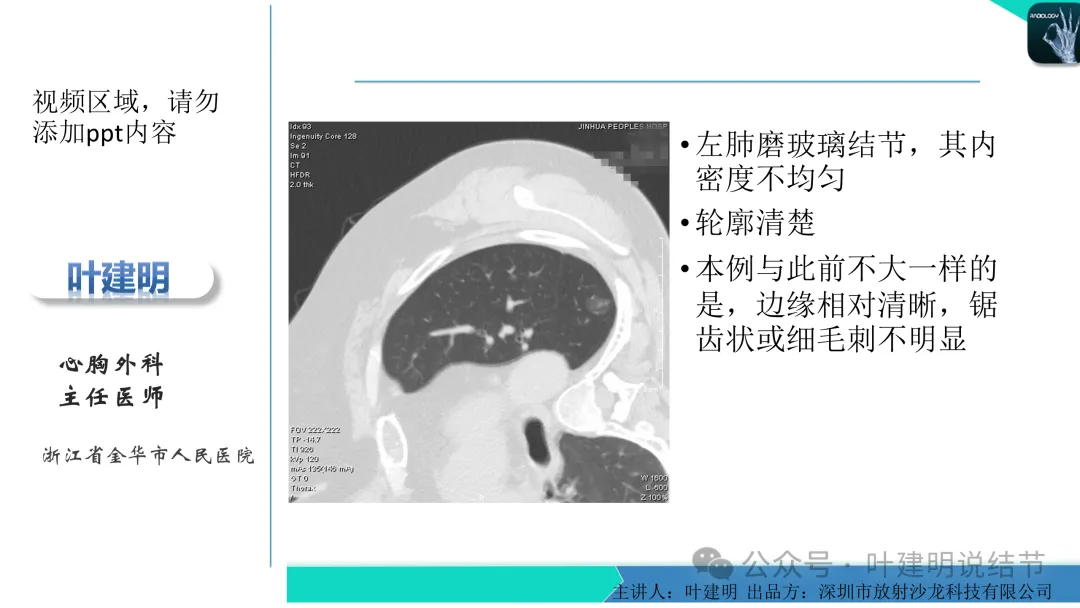

影像展示与分析:

当地说考虑微浸润性腺癌的左下主病灶影像连续层面展示:

病灶出现,显模糊。

上图层面轮廓较清,但密度很淡,似见血管走行,但靠左前方的似条状磨玻璃密度与血管连着的到底是血管分支还是结节的一部分,其实并不确切。如果其实是血管分支,那病灶与它之间就不是空泡。

病灶在此层整体边缘显糊,灶内有空泡似的,瘤肺边界欠清。

边缘不平,还是灶内多发小空泡?邻近血管与之紧贴,但血管无异常走行。病灶密度很低,显糊。

中间所谓空泡更像是细支气管扩张,内壁非常光滑且圆形。

病灶边缘区淡而模糊。

某省胸科医院医生会诊后给出的意见是:左下肺后基底段(结节)达Lung-rads4B类,微浸润性腺癌可能,建议手术干预。签名的是B医生,后面给出了周一A主任肺结节门诊,周四B主任门诊。大概是团队成员,A医生是著名大咖,B医生是团队骨干成员!

这个病灶会是微浸润性腺癌吗?当然没有病理诊断,我也不能说百分之百必不会,但这样的病灶已经风险大到必得尽快手术切除干预了吗?显然还早着呢:1、影像不是典型的结节状;2、边缘与轮廓模糊不清;3、灶内似有细支气管扩张(更容易是细支气管扩张伴少许周围炎或肺泡上皮增生);4、血管邻近走但无牵拉影响;5、没有实性成分,没有锐利毛刺,没有胸膜牵拉,没有血管进入,没有任何倾向风险性高的影像特点。我一直强调:肺结节是否要干预处理,不要纠结于最后病理是什么,而要看风险高低;而风险高低的最重要术前判断依据一是随访有无进展,二是有没有实性成分。只要没有肉眼可见的影像上的实性成分,风险就是低的!何况病理也是人看的,原位还是微浸润,不典型增生还是原位有时也在一念之间。

早在2020年时,我受邀在《放射沙龙》做过一个系列的精品课,当时专门总结分析过各类良恶性肺结节与肿块的影像特征,这是当时关于微浸润性腺癌影像特征的分析,今天看来仍基本不太需要改变,大家有兴趣的可以参考: